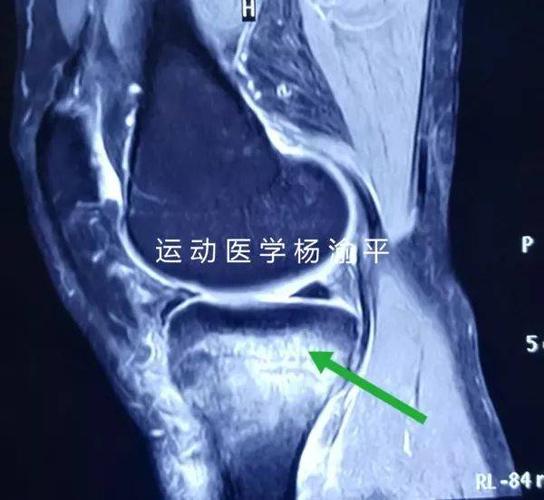

膝关节骨挫伤

患者膝关节磁共振影像,大片白色亮斑即为骨挫伤.

胫骨骨挫伤